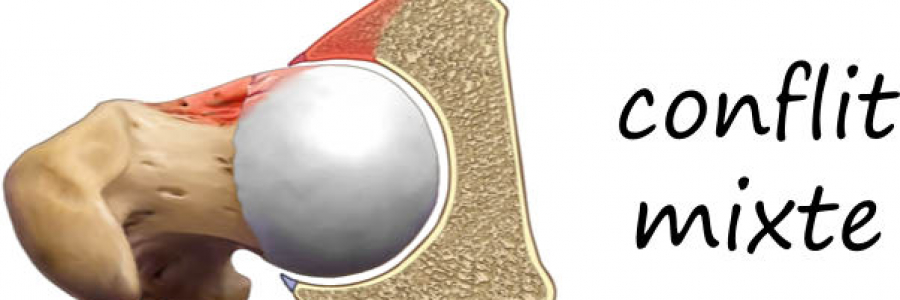

Classiquement il existe 3 formes possibles de conflits fémoro acétabulaires:

- par effet mixte

Il s’y associe presque systématiquement toujours une déchirure du bourrelet cotyloidien (labrum tear).